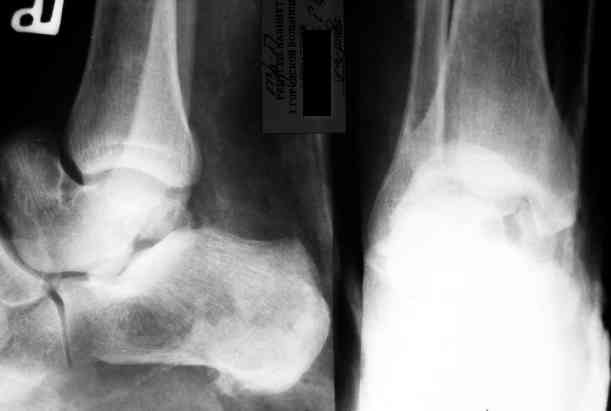

Уважаемый Александр! Как обещал представляю Р-граммы и операционные фото.

Последний снимок

Мнение по поводу тарана? АН есть?

> Мнение по поводу тарана? АН есть?

Типичная картина некроза.

> Операцию планируем на пятницу. План заведующего - двухсуставной

> артродез АВФ. Скину если получится фото и послеоперационные Р-граммы.

Если очаг инфекции - не весь блок, и удастся инфицированную часть хорошо убрать, то будут неплохие шансы на васкуляризацю тарана с двух сторон. Послеоперационные рентгенограммы, конечно, будет интересно посмотреть. Они, правда, вряд ли прогноз надежно отразят.